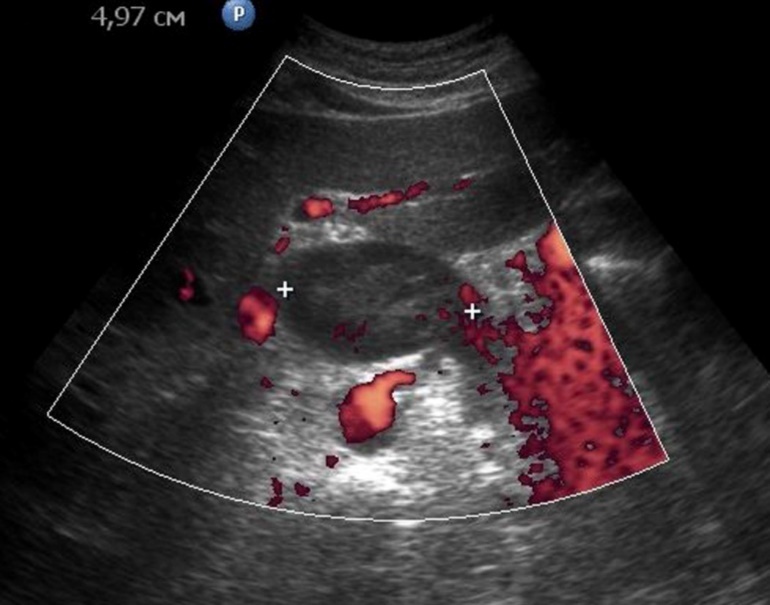

Weak vascularization was manifested in the form of a single point color vascular signals, the moderate vascularization - in the form of linear color vascular signals and the enhanced vascularization - in the form of wide color areas inside the tumor (Figure 16, Figure 17).

Figure 16.Distal gastric carcinomas of diffuse infiltrative form of T4 stage. Despite the large size of the tumor the vascularization is manifested in the form of single point color vascular signals.

Figure 17.Gastric carcinomas of infiltrative ulcerative form of Ts stage. Despite the small size of the tumor the vascularization is manifested in the form of wide color areas inside the tumor.

Among the 61 patients, pathological vascularization was detected in 42 (68.8%) cases. Of these, all 4 (6.5%) patients with gastric cancer were stage T4 and 38 (62.3%) were stage T3. In 13 cases, vascularization was weak, in 24 cases - moderate, and in 5 cases - enhanced.

Color Doppler mode was used to assess the nature of the gastric wall lesion in pathologically thickened areas. This method allows the recording of blood flow in the altered areas and using the degree of vascularization to differentiate gastric cancer and other benign changes. Usually in a normal gastric wall it is not possible to visualize the vessels.